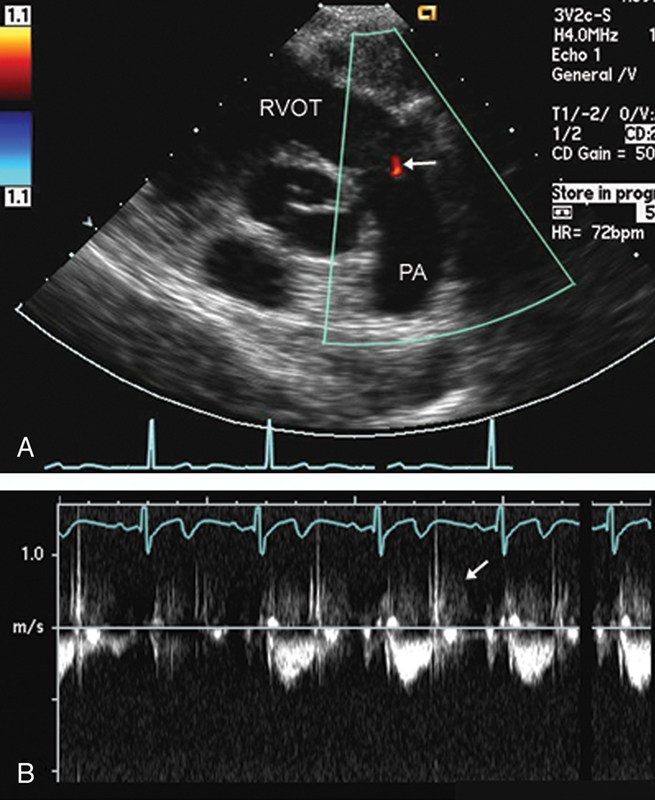

فحوصات تشخيصية لبعض امراض القلب والشرايين التاجية